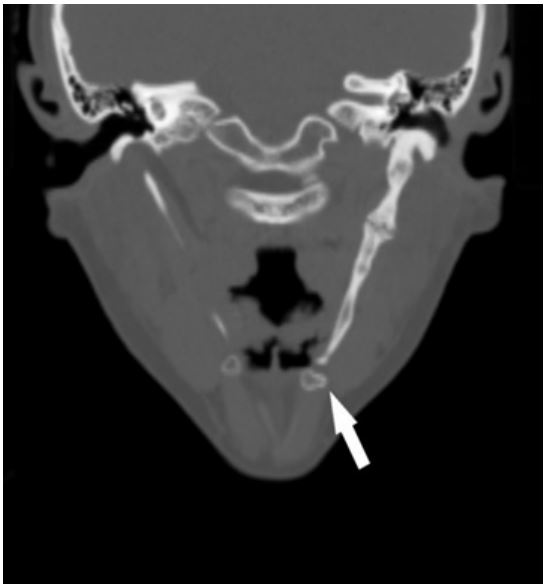

Computed tomography of the neck without contrast administration showed bilateral elongated styloid processes. On the left side the overal lenght of the styloid process was 8,3 cm. Aditionally within the left styloid process we observed two false joints, one of them in the down part, reposition the hyoid bone in caudal direction (Figure 3). Maximum width of the left styloid process was 1,3 cm and it was located at the level of upper false joint. Right styloid process was elongated insignificantly (3,65 cm) and didn’t cause pain or any other symptoms.

Figure 3: Multidetector computer tomography (MDTC) with multi-planar reconstructions (MPR) - coronal view. Reposition the hyoid bone in caudal direction.

The styloid process is a needle-like bony structure protruding anteroinferiorly from the inferior surface of the temporal bone and towards the hyoid bone. On average its length ranges from 2,5 cm to 3,0 cm. When it exceeds 3,0 cm, it is considered elongated. The hyoid bone is a u-shaped bone located in the anterior neck, at the base of the mandible. These two stuctures are connected by stylohyoid ligament and both contribute to the unit called the styloid apparatus, along with associated ligaments and muscles. Anatomiacally they do not make a direct connection with each other. However, the presented case shows a different situation, in which an excessively long styloid process reaches the hyoid and these two form a joint. Altered anatomical relations of the regional structures led to the symptomatic manifestation of Eagle’s syndrome in the patient [1-3,12].